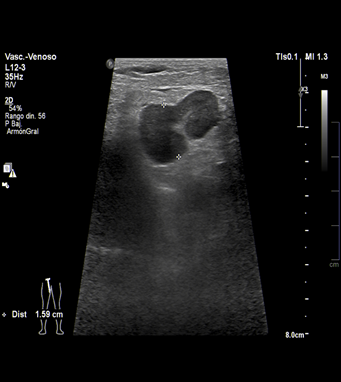

La ecografía es actualmente la técnica de elección para el estudio de la trombosis venosa de las extremidades. No sólo permite un adecuado estudio morfológico de la pared de las venas y de su luz; el Doppler es capaz de valorar en tiempo real y sin necesidad de medios de contraste la presencia y las características del flujo en su interior.

Las imágenes que se muestran corresponden a la ecografía doppler color en el área inguinal izquierda.